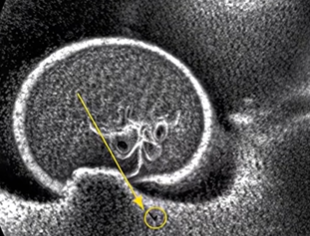

Little Lily had accidentally swallowed several small magnetic pieces from a toy, which had connected inside her intestines and created a potentially dangerous obstruction.